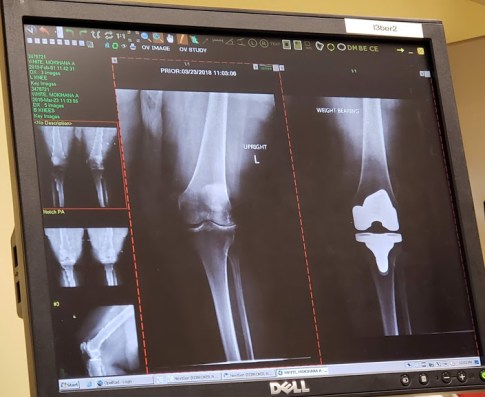

Here’s my x-ray, before and after. I look at it and can hardly believe it. I look at it and think, “OMG, no wonder I hurt!” and I think how grateful I am that my surgeon is so skilled.